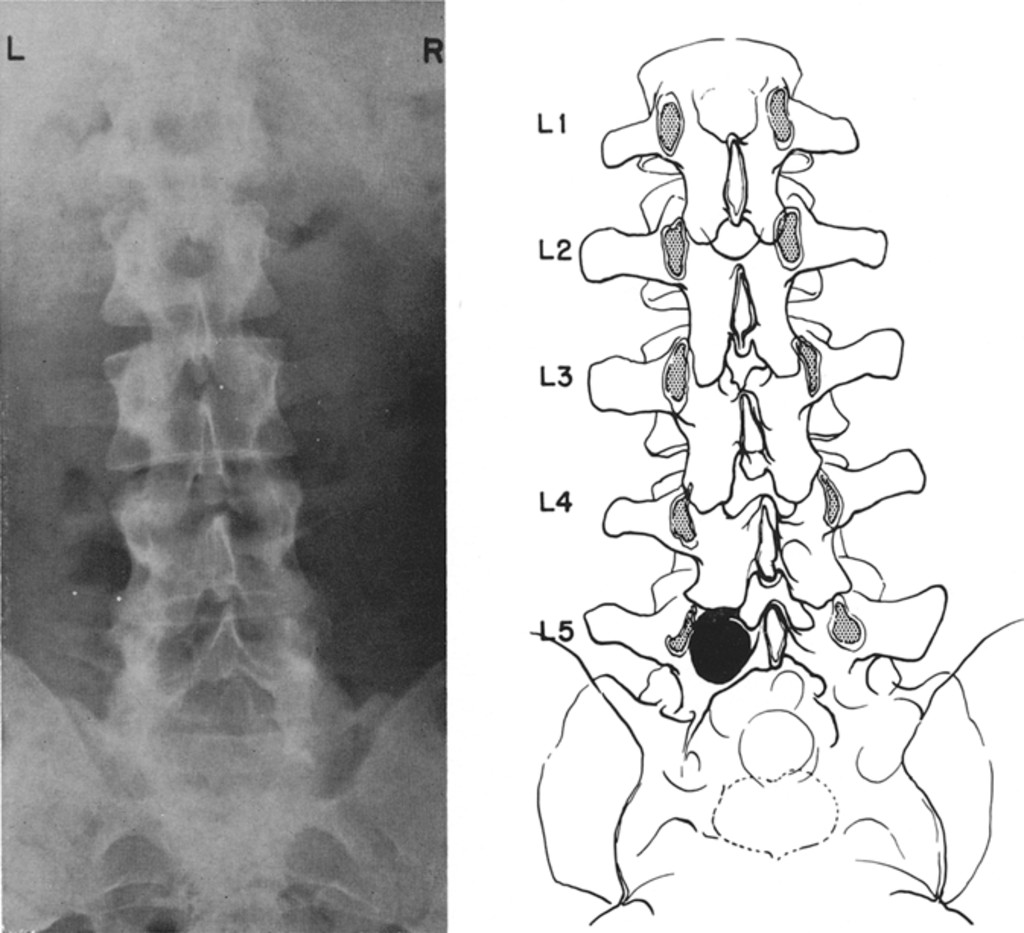

1024x933 Punched Out Erosion Of Lamina - Erosion Drawing

Punched Out Erosion ...